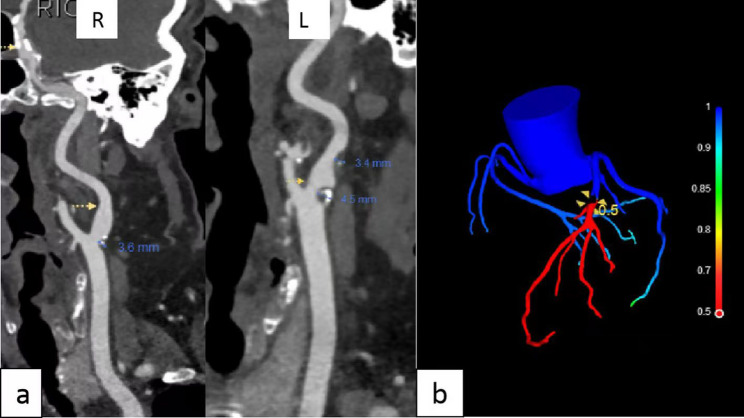

Background: The study aimed to investigate the correlation of carotid plaque and peripheral carotid adipose tissue (PCAT) characteristics with coronary computed tomography-derived fractional flow reserve (CT-FFR) values.

Methods: Data of 136 patients who underwent head and neck computed tomography angiography (CTA) followed by coronary CTA were retrospectively reviewed. Based on their CT-FFR values, they were divided into CT-FFR ≤ 0.8 and CT-FFR > 0.8 groups. The patients' baseline data, carotid plaque and PCAT characteristics were collected. Univariate analysis and multivariate logistic regression were employed to identify differences between groups.

Results: Univariate analysis indicated a statistical differences in carotid plaque thickness, plaque area, plaque load, the carotid plaque Crouse score, minimum plaque density, and net enhancement value of PCAT of patients (P < 0.05). Based on this, multivariate logistic regression analysis demonstrated that carotid plaque thickness (odds ratio (OR) = 0.553; 95% confidence interval (CI) = 0.360-0.847), the carotid plaque Crouse score (OR = 0.653; 95% CI = 0.514-0.830), and net enhancement value of PCAT (OR = 0.820; 95% CI = 0.730-0.919) were independent predictors of the diagnosis of CT-FFR ≤ 0.8. Furthermore, receiver operating characteristic curve analysis showed that the area under the curve of plaque thickness, the carotid plaque Crouse score, and net enhancement value of PCAT for the diagnosis of CT-FFR ≤ 0.8 were 0.816, 0.843, and 0.836, respectively.

Conclusion: Carotid plaque thickness, the carotid plaque Crouse score, and net enhancement value of PCAT are independent related indicators of CT-FFR ≤ 0.8, which can be simultaneously clarified by head and neck CTA alone, as well as the severity of coronary atherosclerosis.